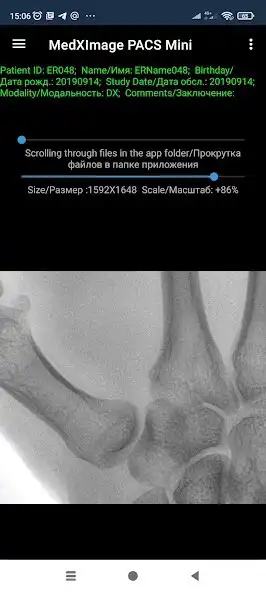

DICOM data loaded into the MedXImage DICOM PACS Mini (PACS (Picture Archiving and Communication System) systems) can be transmitted over the Internet to other systems or to a user with the same application only if the sharing functions are used . The application does not have such functions as worklist, c-move and others, therefore it will not allow access to personal and medical data without the user's permission.

The application allows you to store and view all types of DICOM files, but is intended for DX modality examinations (fluorography, X-ray, and others).

The application has all the necessary functions, such as brightness, contrast, negative, zoom and image rotation, which will allow you to preview the examination.